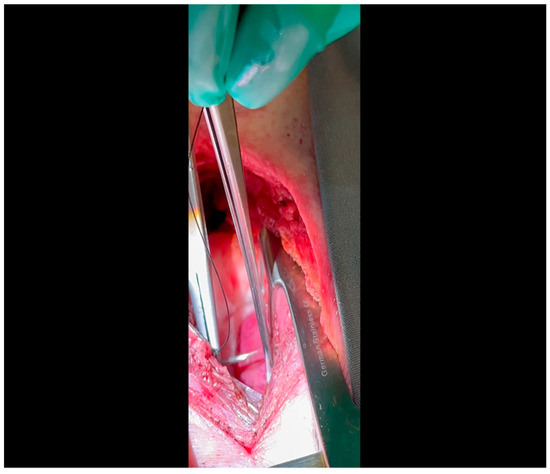

- Electrocautery is used to cut through the skin and muscle of the chest wall. A Weitlaner retractor is used to retract the muscle. The intercostal muscles are divided just above the 3rd or 4th rib (Figure 2), and a Kelly clamp facilitates entry into the parietal pleura and protects the underlying intrathoracic structures as the incision is enlarged; finally, a rib spreader is placed to open the incision.